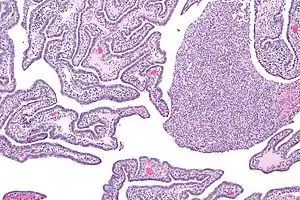

| Micrograph of acute and chronic salpingitis. H&E stain. | |

Acute and chronic salpingitis

There are two types of salpingitis: acute salpingitis and chronic salpingitis.